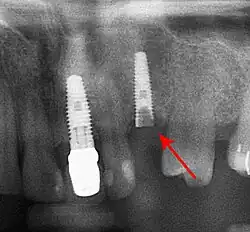

Beyond the possibility of mechanical failure[98] which may be due to poor prosthetic fitment, wear and tear, or user-induced actions such as bruxism, dental implants are also subject to peri-implant mucositis and peri-implantitis, where gum tissue and bone mass around the implant are resorbed, and the implant gradually becomes loose, and has to be removed.[99][100] In addition, although titanium is generally well tolerated by the body, there have been cases where the build-up of titanium particles released by the implant may cause systemic inflammatory response.[101] Because there is no dental enamel on an implant, it does not fail due to cavities like natural teeth. While large-scale, long-term studies are scarce, several systematic reviews estimate the long-term (five to ten years) survival of dental implants at 93–98 percent depending on their clinical use.[15][16][17] During initial development of implant retained teeth, all crowns were attached to the teeth with screws, but more recent advancements have allowed placement of crowns on the abutments with dental cement (akin to placing a crown on a tooth). This has created the potential for cement, that escapes from under the crown during cementation to get caught in the gingiva and create a peri-implantitis (see picture below). While the complication can occur, there does not appear to be any additional peri-implantitis in cement-retained crowns compared to screw-retained crowns overall.[102] In compound implants (two stage implants), between the actual implant and the superstructure (abutment) are gaps and cavities into which bacteria can penetrate from the oral cavity. Later these bacteria will return into the adjacent tissue and can cause periimplantitis.